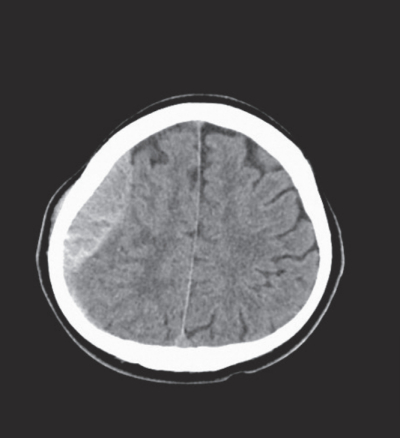

47歳の男性。職場の飲み会の帰りに歩道橋の階段を踏みはずして受傷し、救急車で搬入された。

来院時の意識レベルはJCS II-10。体温 36.6 ℃。血圧 126/88 mmHg。心拍数 80/分、整。呼吸数 16/分。SpO2 99%(リザーバー付マスク10L/分 酸素投与下)。来院時に緊急で撮影された頭部単純CTの水平断像と冠状断像および骨条件の水平断像と冠状断像を別に示す。

診断はどれか。2つ選べ。

a. 頭蓋骨骨折

b. 急性硬膜外血腫

c. 急性硬膜下血腫

d. 外傷性脳内血腫

e. びまん性軸索損傷